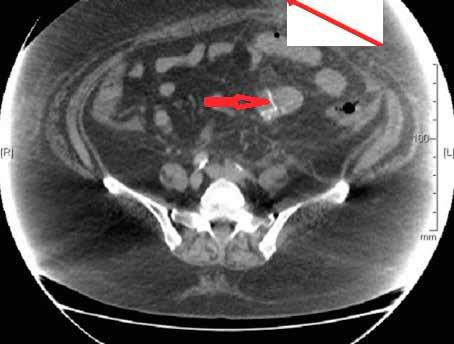

图3 腹部CT提示小肠内存在结石

一名49岁的女性患者因上腹部疼痛伴恶性呕吐于当地医院急诊科就诊,两个月前患者因胆石症,胆总管扩张,梗阻性黄疸行内镜逆行行胰胆管造影术,,取出3块胆石,如图1、2。行腹部CT检查,提示小肠梗阻,胆石性肠梗阻,十二指肠瘘,如图3、4。患者立即行急诊手术治疗,术中发现扩张小肠有明显胆石阻塞及压迫痕迹,取出胆石,由于小肠压力过大,出现部分坏死,因此行小肠部分切除术,如图5。在距离回盲部60cm小肠处取出大小约3.5cm*3.5cm胆结石,如图3。用腹腔镜从Treitz韧带检查小肠,并未发现有残余结石,病人在手术后已康复,顺利出院。